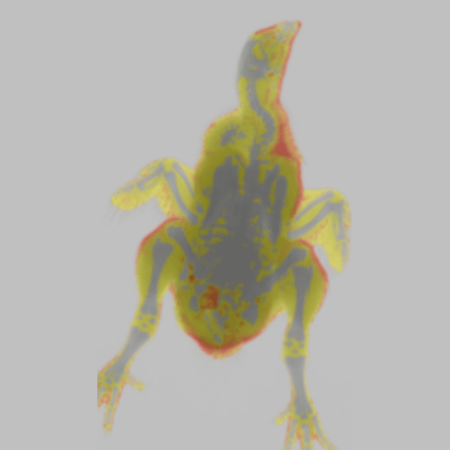

The iNSiGHT technology employs dual energy X-rays to provide highly accurate and repeatable body composition assessments. The system categorizes each pixel into one of three compartments: fat mass, non-bone/lean mass, or bone mineral content, and provides measurements such as bone mineral density, bone mineral content, bone area, tissue area, fat tissue percentage and weight, lean tissue percentage and weight, and total weight in grams.

The X-ray attenuated image, bone mineral density map, and color map are produced in a single scan (25 seconds).

The iNSiGHT system measures changes in fat and lean mass over time to assess disease progression or regression and body composition assessments in response to a treatment program. The colorimetric image distinguishes visceral and subcutaneous fat using regions of interest, which could be useful in further understanding these diseases.

The iNSiGHT system can evaluate changes in body composition parameters following hypoxia exposure. The colorimetric image allows for distinguishing visceral and subcutaneous fat using regions of interest, which may help understand the metabolic effects of such exposures. In this case, hypoxia exposure reduces the amount of fat in mice.

Bone Mineral Density Image - Rat. Image Credit: Scintica Instrumentation Inc